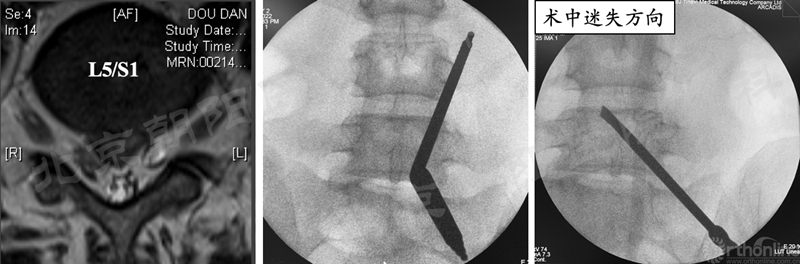

2、 镜下迷失——节段错误

#14例UBE,术中迷路,L5/S1突出做到了L4/5右侧透视图),及时转开放减压。

本例手术镜下迷失原因总结:

① 术前设计切口靠近端,本期望利于椎板钳减压椎板,弄巧成拙;

② 定位后通道方向没有记牢,操作时角度改变了;

③ 做L5/S1体位摆放应注意把上半身摇高,使L5/S1水平;

透视正位应将L5/S1间隙标准化,否则定位不准;

⑤ 患者肥胖,脂肪软组织厚;

⑥ 镜下结构不对马上透视。